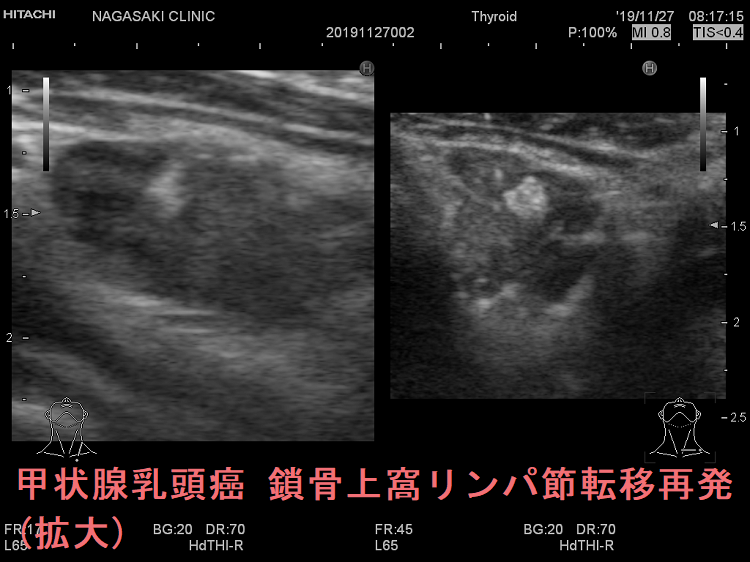

甲状腺乳頭癌の鎖骨上窩リンパ節転移再発 超音波(エコー)画像

鎖骨上窩は予防的リンパ節郭清(前頚部リンパ節郭清)の範囲外につき、術後リンパ節再発のピットフォールとなります(意外とよく見つかります)。

甲状腺乳頭癌が左鎖骨上窩リンパ節に転移して再発すると、左静脈角から血流に乗って全身へ運ばれ、遠隔転移を来します。左鎖骨上窩の転移リンパ節をウィルヒョウリンパ節、左鎖骨上窩リンパ節転移をウィルヒョウ転移と言います。

甲状腺乳頭癌 左鎖骨上窩リンパ節転移再発

甲状腺乳頭癌 左鎖骨上窩リンパ節転移再発;いびつな形で、リンパ門は消失。内部に異常な走行の血管を認め、血流豊富。

ケース③

甲状腺乳頭癌 左鎖骨上窩リンパ節転移再発 超音波(エコー)画像

甲状腺乳頭癌 左鎖骨上窩リンパ節転移 超音波(エコー)画像;いびつな形で、リンパ門の痕跡あり。砂粒状石灰化も認める。

甲状腺乳頭癌 左鎖骨上窩リンパ節転移再発 超音波(エコー)画像(拡大)

甲状腺乳頭癌 左鎖骨上窩リンパ節転移 超音波(エコー)画像 (拡大)